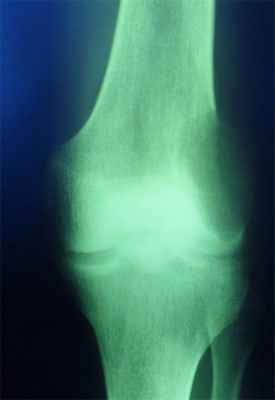

Заболевания по направлению Повреждение мыщелков бедренной кости

Повреждение мыщелков бедренной кости возникает при прямом действии травмирующего агента. Чаще всего, такая травма возникает в результате удара по колену или падении на него. Также, перелом мыщелков происходит при падении с высоты.

Мыщелок - парный фрагмент бедренной кости, который находится в её нижней части и формирует коленный сустав. Различают медиальный (ближе к срединной оси тела) и латеральный (боковой) мыщелки. Их переломы делятся на низко- и высокоэнергетические, в зависимости от характера травмы. Может наблюдаться изолированный перелом одного из мыщелков или их комбинированное повреждение. некоторые переломы сопровождаются образованием осколков.

Как распознать перелом мыщелка бедренной кости?

Основной синдром при данном повреждении - болевой. Локализация болезненности - коленный сустав, который становится более сглаженным и теряет привычные контуры;

Внутреннее кровоизлияние приводит к выпячиванию тканей, отеку, болезненности при пальпации;

Нажатие на надколенник дает возможность почувствовать его непривычное положение и то, как он “пружинит” под давлением собравшейся внутри сустава крови;

Если произошло смещение мыщелка, это отражается на отклонении голени в сторону;

Пациент не может совершать активные движения, а пассивные вызывают резкую боль.

Подобные симптомы сопровождают переломы надколенника, мыщелков голени, а также растяжение связок колена и повреждение мениска. Поэтому для точной постановки диагноза требуется дополнительная диагностика. Отличием переломов мыщелков бедра от повреждения аналогичных структур голени является тот факт, что в первом случае боль локализуется выше суставной щели колена, а во втором - ниже её.

Диагностика патологии

Диагностика осуществляется на основе клинических данных и дополнительных методов исследования. Начинается постановка диагноза с опроса пациента и осмотра. Врач отмечает визуальные признаки переломов, характерные для повреждения мыщелков. Во время сбора анамнеза необходимо уделить должное внимание характеру полученной травмы, поэтому пациент четко должен описывать её в разговоре с врачом.

“Золотым стандартом” является выполнение рентгенограммы. Снимок делают в двух проекциях - прямой и боковой. Есть еще дополнительные методы исследования, но к ним прибегают реже.

Если данные рентгеновского снимка малоинформативны или есть сомнения - проводится томография на компьютерном аппарате.

Магнитно-резонансная томография не дает необходимых данных о состоянии кости - к этому методу прибегают, если есть риск повреждения мягких тканей и необходимо исключить их травму.